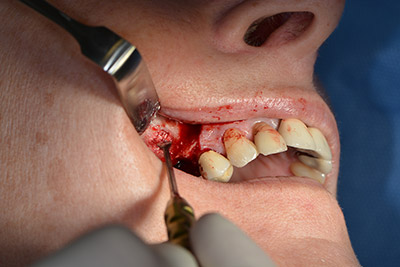

The classic incision (crestal, buccal relief) and the preparation of the mucoperiosteal flap enabled a good overview.

Sky implants (bredent) were used this case. The surgical protocol of these, specify pilot drilling at about 1200 rpm (Fig. 9).

The following holes were drilled at a reduced speed of 300 rpm. The Implantmed demonstrated its true capability at this stage. The surgical protocol can be preset – the various positions can be selected simply by pressing the “P” position of the foot control (Fig. 10 to 11).